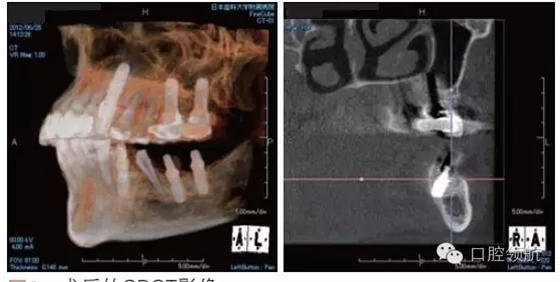

利用曲面斷層及CBCT檢查埋入部位情況,雖未出現(xiàn)與主訴相關(guān)的神經(jīng)損傷,但無意中卻發(fā)現(xiàn)了種植體的舌側(cè)穿孔(圖1、圖2)。

圖2 術(shù)后的CBCT影像。

雖不能確定是裂鉆備洞還是植入種植體所造成的穿孔,但從4個月的病情的發(fā)展看,考慮可能是術(shù)中的舌下動脈損傷導(dǎo)致口底軟組織內(nèi)出血而造成的感覺異常。采用常規(guī)藥物及物理療法開始進(jìn)行治療。